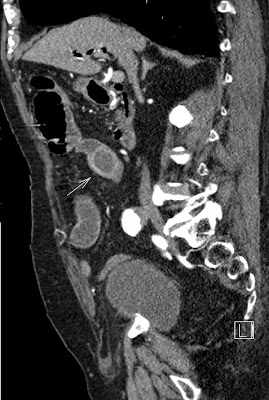

Gallstone ileus Szerző: admin | okt 1, 2012 | Biliary tract, Ileus | Nincsenek hozzászólások air in the gallbladder after perforation (short arrow), gallstone in the small intestine (long arrow) dilatation of the small bowel loops on the left (proximal to the impacted gallstone) 2012.09.28.69789